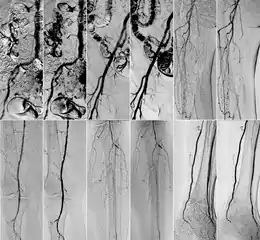

In 2018 Gyánó M. et al. compared the quality of DVA and DSA (digital subtraction angiography) images in a prospective observational crossover study, which involved the analysis of 232 image pairs of 42 patients undergoing lower limb x-ray angiography (performed by using iodinated contrast agent) between February and June 2017. Methods included the measurement of SNR (signal-to-noise ratio) and visual quality comparison.[1]

Qualitative comparison has been performed by three vascular surgeons and three interventional radiologists, with about 17 years of experience on the average. In an online visual questionnaire, which showed DVA and DSA image pairs of the same anatomical regions, raters were asked to choose the image which they found to be more useful for making the diagnosis. Overall, the raters judged the kinetic images better in 69 % of all images. Regarding different anatomical regions, the raters agreed that the DVA was significantly better for talocrural and popliteal regions.